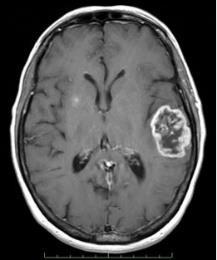

Abstract - Detecting brain tumors via Magnetic Resonance Imaging (MRI) is crucial but challenging due to the intricate nature of these abnormalities. A proposed method involves several steps, including sigma filtering, adaptive thresholding, and region detection, to analyze MR images. Shape features such as Major Axis Length, Euler Number, Minor Axis Length, Solidity, Area, and Circularity are extracted to characterize the tumors. This method employs two supervised classifiers: a C4.5 decision tree algorithm and a Multi-Layer Perceptron (MLP) algorithm. These classifiers distinguish between normal and abnormal brain cases, with abnormalities further classified into benign or malignant tumors. With a dataset of 250 brain MR images, the MLP algorithm achieves a notable precision of approximately 80%.

Brain tumors are solid neoplasms found within the skull, arisingfromuncontrolledandabnormalcelldivision.They typicallydevelopinthebrainitself,butcanalsomanifestin other locations such as lymphatic tissue, blood vessels, cranial nerves, and brain envelopes. Additionally, brain tumorscanresultfromthemetastasisofcancersoriginating elsewhere in the body. The classification of brain tumors hinges on factors like their location, the tissue type from whichtheyoriginate,theirmalignantorbenignnature,and otherconsiderations.

Primary brain tumors originate within the brain and are named based on the cell types from which they originate. They may be benign, such as Meningioma, which cannot metastasize.Conversely,theycanbemalignantandinvasive, exemplified by Lymphoma (characterized by a ring-like appearance),cysticoligodendroglioma(displayingrounded cellswithdistinctbordersandacentralnucleusresembling a"friedegg"),Ependymoma(arisingfromependymalcells andexhibitingmalignantbehaviordespitebenignhistology), and Anaplastic astrocytoma (a common high-grade astrocytoma).

Secondary brain tumors, also known as metastatic brain tumors,developfromcancercellsthathavemigratedtothe brainfromotherpartsofthebody.Typically,thesecancers

originate from primary tumors in organs such as the kidneys, lungs, breasts, or from melanomas on the skin. A brain scan offers a detailed visualization of the brain's internal structure. Among the most frequently utilized methods for brain imaging is MRI (Magnetic Resonance Imaging), renowned for its ability to provide exceptional insightsintothehumanbody.TocategorizeMRImages,two primary methodologies are employed: supervised techniques like support vector machines, k-nearest neighbors,andartificialneuralnetworks,andunsupervised techniquessuchasfuzzyc-meansandself-organizingmaps (SOM). Many studies have utilized a combination of both supervisedandunsupervisedtechniquestodistinguishMR Imagesas either normal or abnormal.Thisstudy employs supervisedmachinelearningtechniquestocategorizefive distinct types of abnormal brain MR Images, including Ependymoma, Lymphoma, Cystic Oligodendroglioma, Meningioma,andAnaplasticAstrocytoma,alongsidenormal images